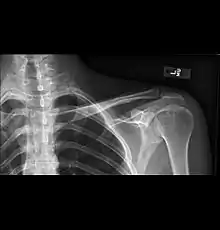

AP radiograph demonstrating companion shadow of the clavicle

- Clavicular companion shadow is a thin soft-tissue stripe along the upper edge of the clavicle.[1]